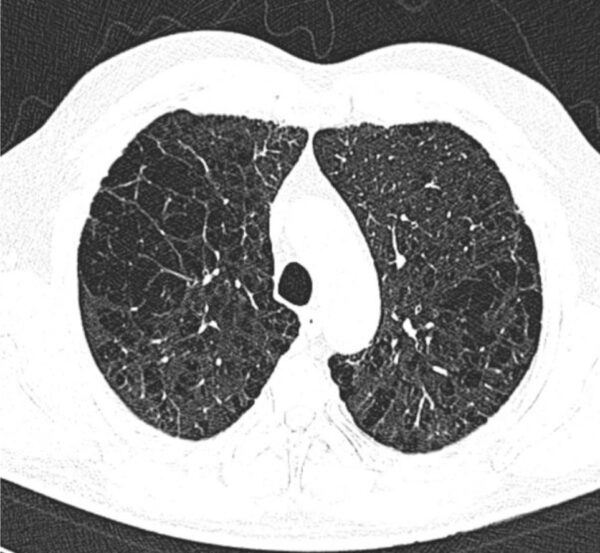

https://radiopaedia.org/cases/alpha-1-antitrypsin-deficiency-15

Modality

CT

Region

CHEST